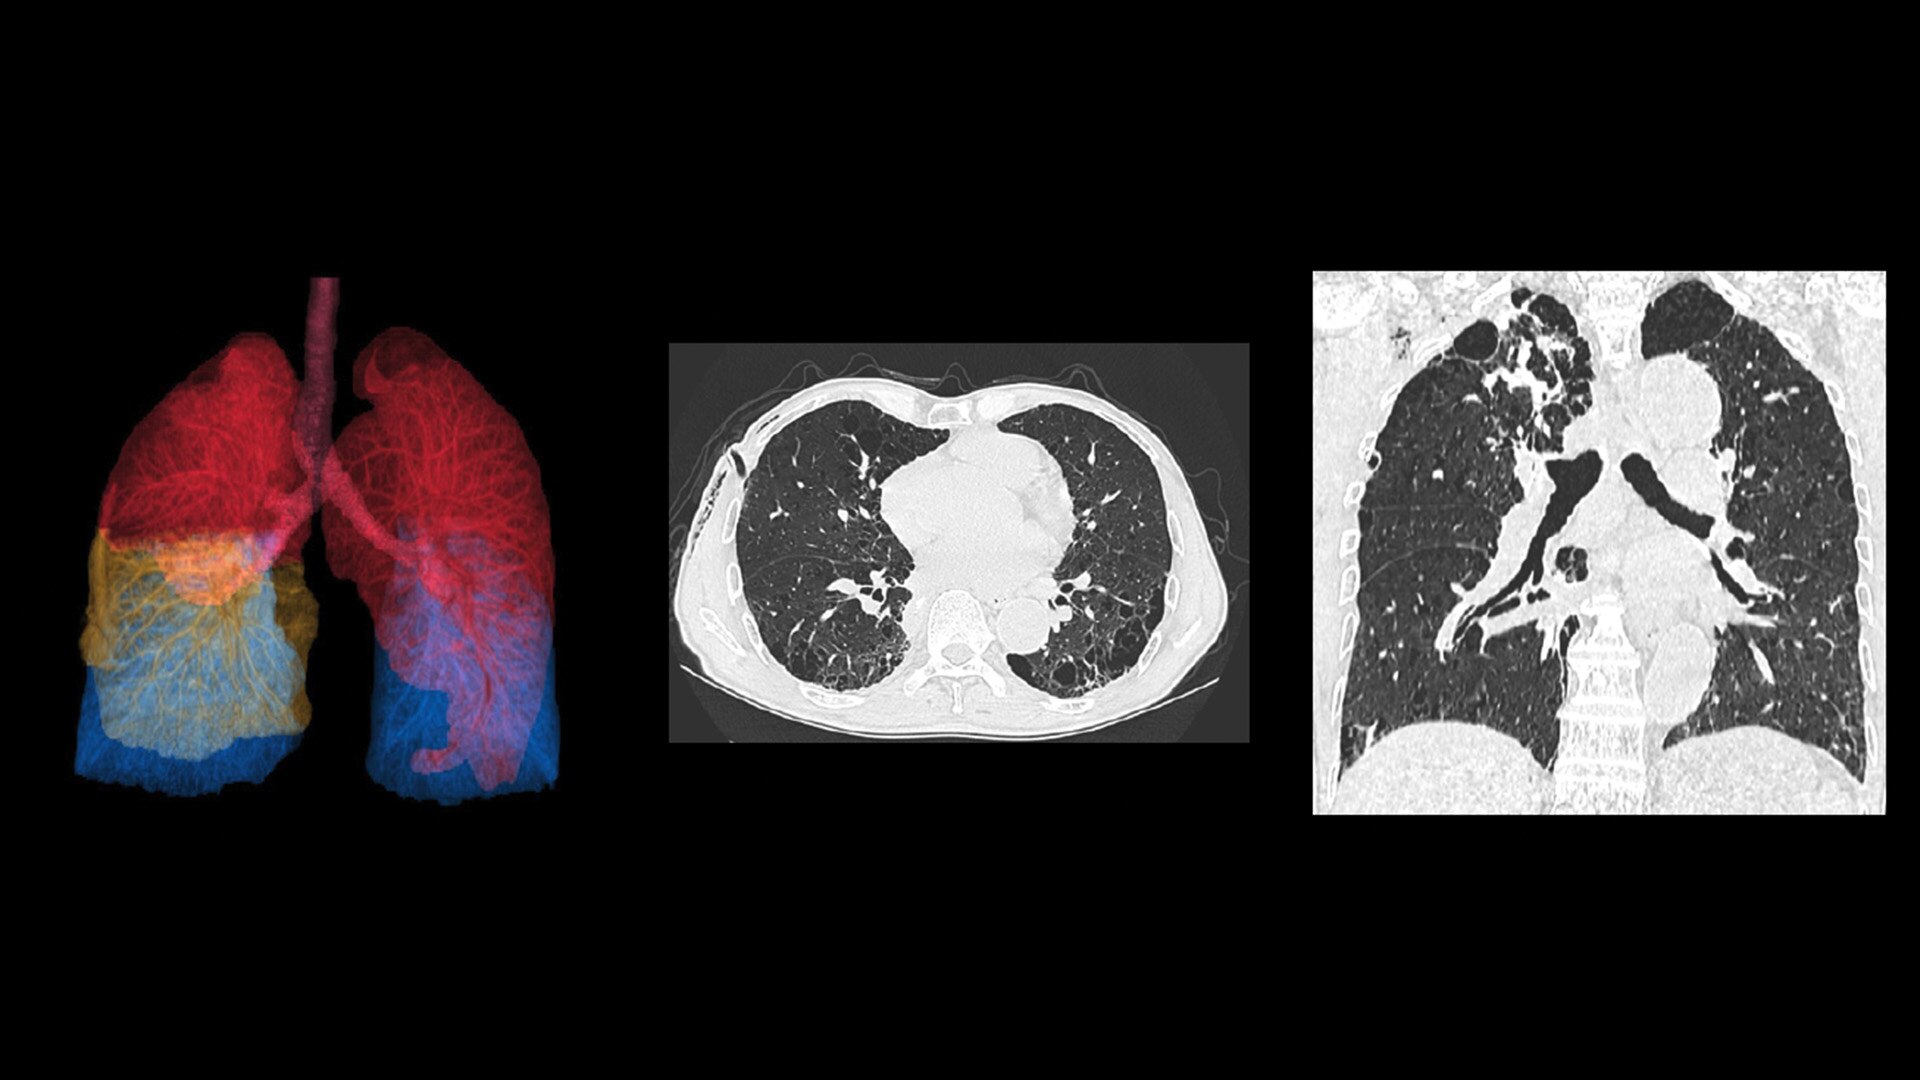

When it comes to imaging more challenging cases, such as neuro, oncology or pediatric patients, VISR3. (Volumetric Image Space Reconstruction) reduces noise without impacting image resolution. This means less dose for the patient while maintaining the high-image quality you need for more accurate diagnoses.